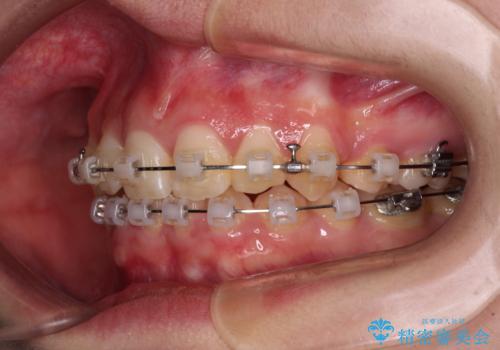

- 矯正装置

- クリアブラケット

上顎左右第一小臼歯2本を抜歯し、ワイヤー装置にて矯正治療を行うこととしました。

通常の抜歯矯正と抜くべき歯の位置が異なるため、咬みにくさが残ってしまうのではないかと懸念されましたが、咬み合わせに違和感なく、スムーズに治療を終えることができました。